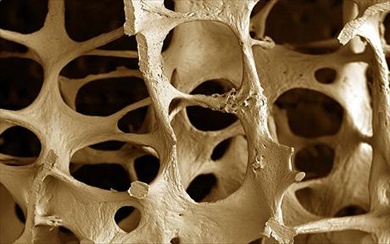

Dopo i 50 anni una donna su tre e un uomo su cinque sono destinati a subire delle fratture a causa della fragilita’ ossea, solo in Italia l’osteoporosi interessa circa 5 milioni di persone, numero destinato ad aumentare poiche’ legato al progressivo invecchiamento della popolazione. L’osteoporosi e’ una patologia principalmente femminile e che riguarda soprattutto le donne in post menopausaa causa del calo di produzione di estrogeni, fondamentali per la salute ossea. In menopausa la produzione di estrogeni cala con una conseguente progressiva perdita di massa ossea. Questo fenomeno e’ evidente gia’ qualche anno prima della menopausa, poi nei primi anni post menopausali si verifica una perdita di massa ossea annuale che va dal 2 al 5% della densita’ minerale ossea (BMD) misurata. La patologia, in post menopausa, si puo’ manifestare con dolori ossei, mal di schiena, cifosi diminuzione dell’altezza e diventare causa di fratture e deve essere trattata ma ancor di piu’ combattuta con una buona prevenzione. La prevenzione che oltre ai regolari esami clinici di controllo, si traduce in corretti stili di vita e alimentari da adottare fin dalla giovane eta’. Per quanto riguarda l’alimentazione questa deve essere varia e bilanciata e per la salute dell’osso deve essere ricca di calcio e vitamina D. Ma non solo, un nutriente fondamentale per le articolazioni e le ossa e’ il collagene, proteina presente naturalmente nel nostro organismo. Gli alimenti ricchi di collagene sono i brodi, la trippa a gelatina di pesce o di carne. “Purtroppo con l’avanzare dell’eta’ il nostro organismo produce meno collagene e l’alimentazione da sola non basta per sopperire questo calo fisiologico. Un aiuto in piu’ arriva da una regolare integrazione di collagene idrolizzato. Ricavato dalla cartilagine e da altri tessuti connettivi animali, questo tipo di integratore e’ ottenuto attraverso l’idrolisi, un processo che rende le molecole della proteina piu’ piccole e leggere e, di conseguenza, maggiormente assimilabili a livello intestinale” spiega Andrea Cappelletti di Protein SA, una delle maggiori aziende europee di prodotti a base di collagene idrolizzato, tra cui Colpropur. Studi scientifici indicano che il collagene idrolizzato, se preso in quantita’ di 10 gr al giorno in modo regolare, agisce favorevolmente su massa muscolare e densita’ ossea. Il tempo che intercorre tra l’inizio dell’assunzione regolare e la percezione degli effetti positivi dipende dall’eta’ del soggetto e dalla sua condizione di salute. Generalmente e’ possibile riscontrare una differenza gia’ tra il secondo e il terzo mese dopo l’inizio dell’utilizzo regolare dell’integratore.

Sanità. 5 mln in Italia soffrono osteoporosi, un aiuto da collagene

Dopo i 50 anni una donna su tre e un uomo su cinque sono destinati a subire delle fratture a causa della fragilita’ ossea, solo in Italia l’osteoporosi interessa circa 5 milioni di persone, numero destinato ad aumentare poiche’ legato al progressivo invecchiamento della popolazione. L’osteoporosi e’ una patologia principalmente femminile e che riguarda soprattutto […]